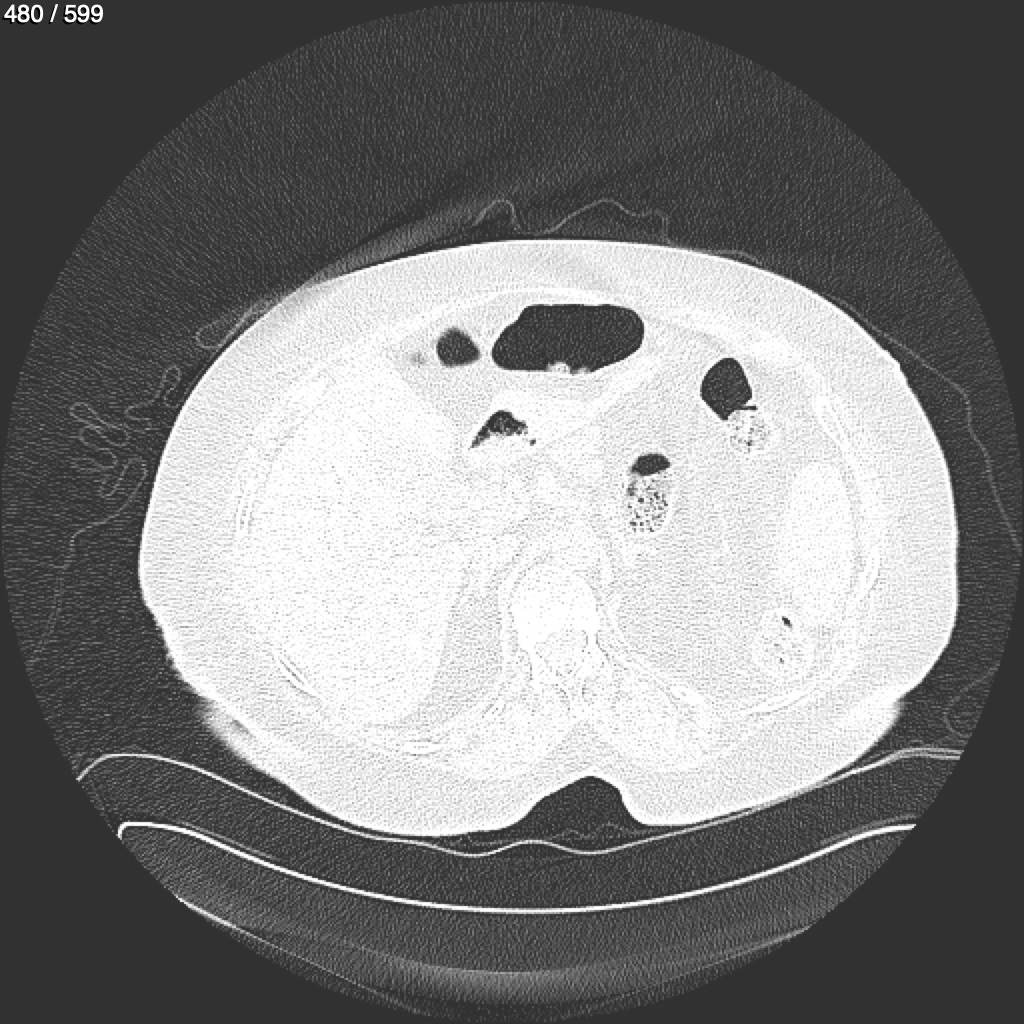

Home G​l​o​r​i​a​ ​G​l​a​d​y​s​ ​B​e​a​s​l​e​y​ ​-​ ​T​ó​r​a​x​ ​T​o​r​a​x​_​S​i​m​p​l​e​ ​(​A​d​u​l​t​o​)